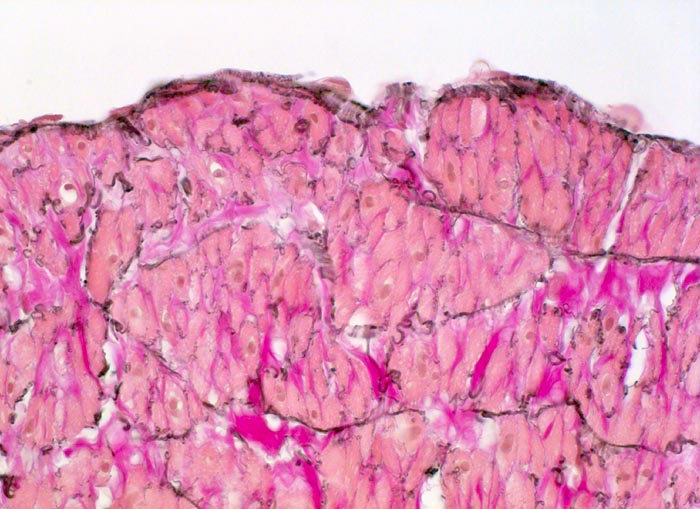

PathoPic ID 5067 - normale Venenwand: Endothel

normale Venenwand: Endothel

Vene

Kardiovaskuläres System

Flache

Endothelzellen der Intima grenzen unmittelbar an die glatte Muskulatur durchsetzt von elastischen Fasern der Media.

Im Gegensatz zu den Arterien ist die Intima (Endothel und subendotheliales Bindegewebe) der Vene sehr dünn.

Histologie

400